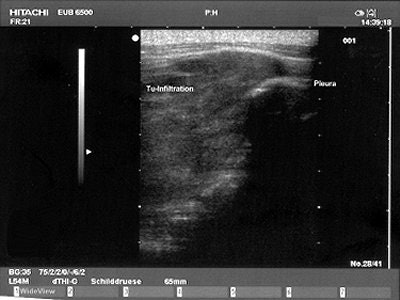

| A Brustwand echocardiogram depicting infiltrating carcinoma. |

"Pleural mesothelioma presents sonographically as an irregularly limited, echo-poor, knotty, or planar widening along the pleura," Herth wrote in Lung Cancer. "An increase in the pleural thickness, however, suggests the likelihood of malignancy. A widening of the pleura of more than 1 cm is considered highly indicative of the presence of malignant tumor" (August 2004, Vol. 45:1 supplement, pp. S63-67).

| Mesothelioma on ultrasound. Images courtesy of Dr. Felix Herth. |